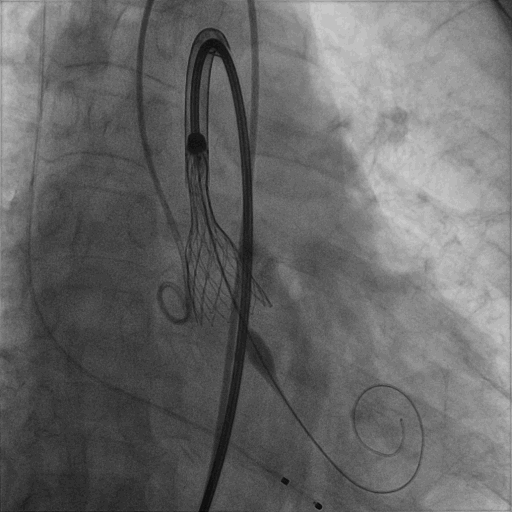

部分回收后,对人工瓣膜重新定位并释放,位置理想且基本与瓣环齐平。

术后即刻TTE显示

主动脉瓣少量瓣周漏,PGmean:7 mmHg,Vmax:1.97m/s,瓣口面积:1.9mm²,LVEF:70.8% 。

本例手术充分体现浙江大学医学院附属第二医院心脏瓣膜中心的精湛技术与高精实力,团队协作娴熟默契,瓣膜植入过程不到10分钟,手术获得圆满成功。再次印证“杭州方案”对二叶式主动脉瓣狭窄TAVR手术是安全且有效的治疗策略。术后王建安书记对TaurusElite™经导管主动脉瓣系统的瓣膜平衡的综合表现及可回收性能给予高度评价。